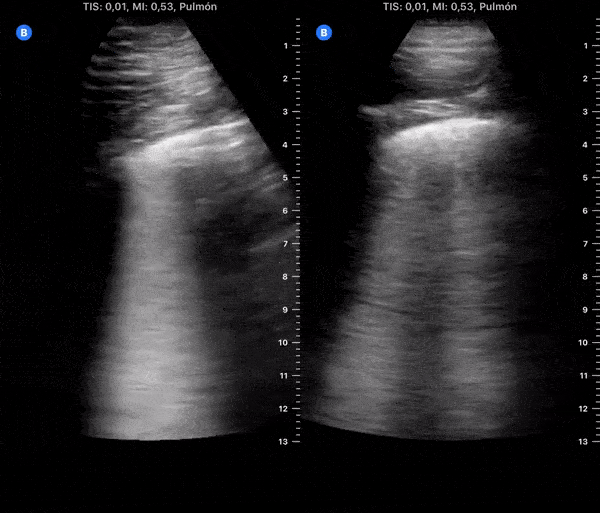

COVID 19 Lung US Disease Progression - Day 9

Day 9 after #COVID diagnosis. Feeling slightly better. More cough. No dyspnea or red flag symptoms. No fever. SpO2 97%. #POCUS update: similar to yesterday. Left lower & lateral with thick pleural line & focal B-lines. @yaletung